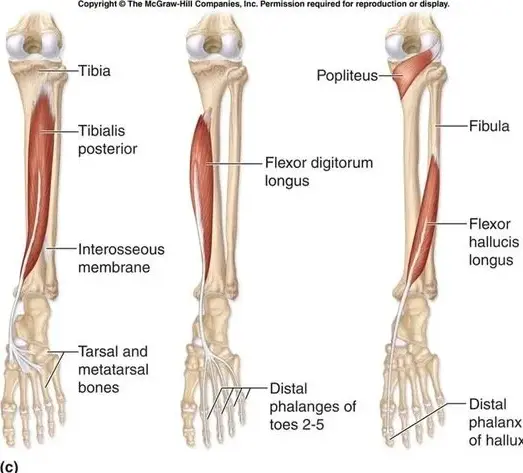

The focus of this article is hips, but Part I of this blog was all about the fabulous feet. I should mention that problems walking and running can arise if you have inadequate muscle flexibility in the calf muscles (or the foot and ankle joint complex), and therefore you may lack the ability to load weight and transfer it through your foot for a good strong push-off. Tight ankle and foot joints or tight calf muscles can contribute to toeing out and loading improperly through your arch or stressing the Tibialis Posterior muscle (see photo ) which can progress to shin splints, or placing improper stress on your big toe joint, leading to, or worsening bunions.